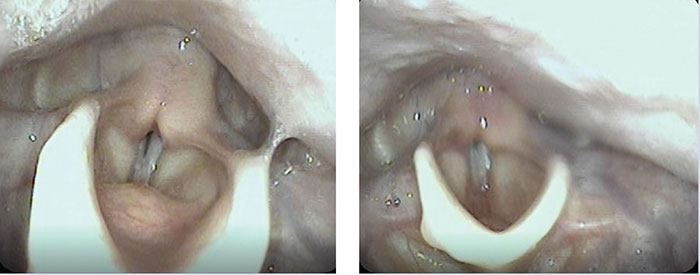

Injection laryngoplasty is minimally invasive and may use hyaluronic acid, calcium hydroxyapatite, gel or other implants to obtain glottal closure. FIGURE 1 shows the glottis before and after hyaluronic acid injection augmentation of the vocal cord. Post-operative assessment of vocal cord function, voice quality and patient-reported outcomes is complex and multi-dimensional, but many studies show it is effective in some but not all patients.20 Assessment includes perceptual, acoustic and aerodynamic assessment, as well as direct endoscopic visualisation.21 In writing this review, we did not find any large case series of injection laryngoplasty in children or adults who were born preterm.

FIGURE 1 Endoscopic images of the larynx of an ex-preterm born at 26 weeks’ gestation with left vocal cord paralysis after PDA ligation. Left: Pre-operative image showing A = left vocal cord, B = right vocal cord and C = left arytenoid. Notice the prolapsed left arytenoid due to palsy. Right: Left vocal cord augmentation with hyaluronic acid, X = site of hyaluronic acid.